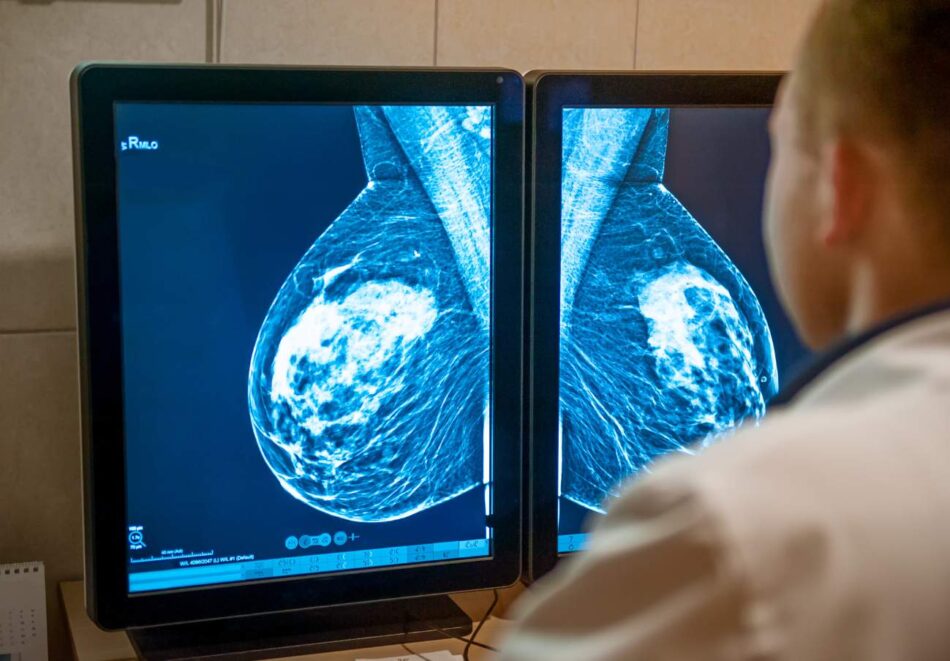

La afectada, una sevillana de 59 años, acudió a revisión en junio de 2024 en el marco del Programa de Detección Precoz de cáncer de mama, donde le encontraron «hallazgos que recomiendan ampliar el estudio». No ha vuelto a tener noticias hasta octubre de este año.

El hallazgo en concreto era un nódulo de «densidad media» encontrado en la mama derecha. Aunque el primer diagnóstico señalaba que la «lesión» encontrada era «benigna (Cat. 2)», se recomendaba realizar una derivación hospitalaria para una «tomosíntesis» (mamografía 3D) y ecografía.